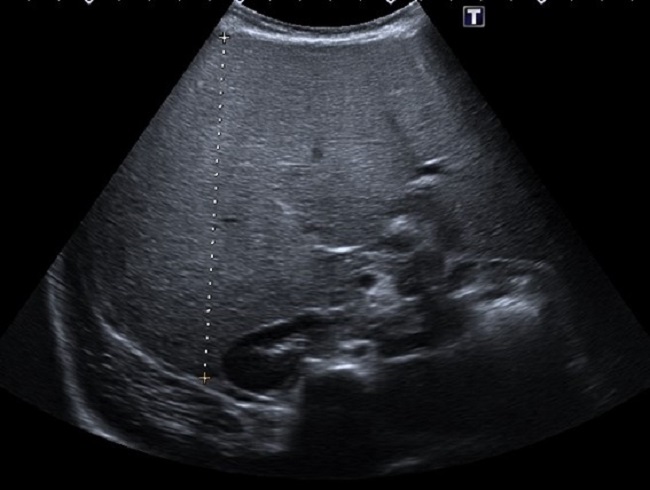

En la anamnesis, llama la atención la hiperfagia. Los padres refieren que come con mucho apetito y tiene hambre casi constantemente. También, la irritabilidad nocturna y la tendencia diaforética. En la exploración física, presenta aspecto macrosómico, con prominente panículo adiposo. Buena coloración de piel y mucosas, no ictericia. Abdomen distendido con hepatomegalia masiva de consistencia firme, hasta 12 cm bajo el reborde costal. No hay esplenomegalia. Exploración neurológica normal. En los análisis de sangre, presenta hipoglucemia (20 mg/dl) y elevación de transaminasas (GPT 289 U/l, GOT 550 U/l, GGT 125 U/l), hipertrigliceridemia (240 mg/dl) e hipercolesterolemia (280 mg/dl), creatin cinasa (CK) 89 U/l, lactato 1,3 mmol/l; con estudio de virus hepatotropos y autoinmunidad negativos. Estudio de coagulación normal. En la ecografía abdominal se visualiza una hepatomegalia masiva, con hiperecogenicidad difusa (Fig. 1)y (Fig. 2). Ecocardiografía y exploración oftalmológica normales. Durante el ingreso, se llevan a cabo controles glucémicos, constatándose numerosas hipoglucemias de ayuno, todas ellas asintomáticas. Ante la sospecha de glucogenosis, se instaura tratamiento dietético con optimización de la ingesta de hidratos de carbono de absorción lenta, con lo que se consigue controles de glucemia normales previos al alta. Se realiza estudio metabólico sugerente de glucogenosis (oligosacáridos en orina: excreción elevada de hex4). En el estudio genético se objetiva variante patogénica c.556G>T(p.E186*) en el gen PHKG2 en aparente homocigosis, compatible con el diagnóstico de enfermedad de almacenamiento de glucógeno tipo 9C.